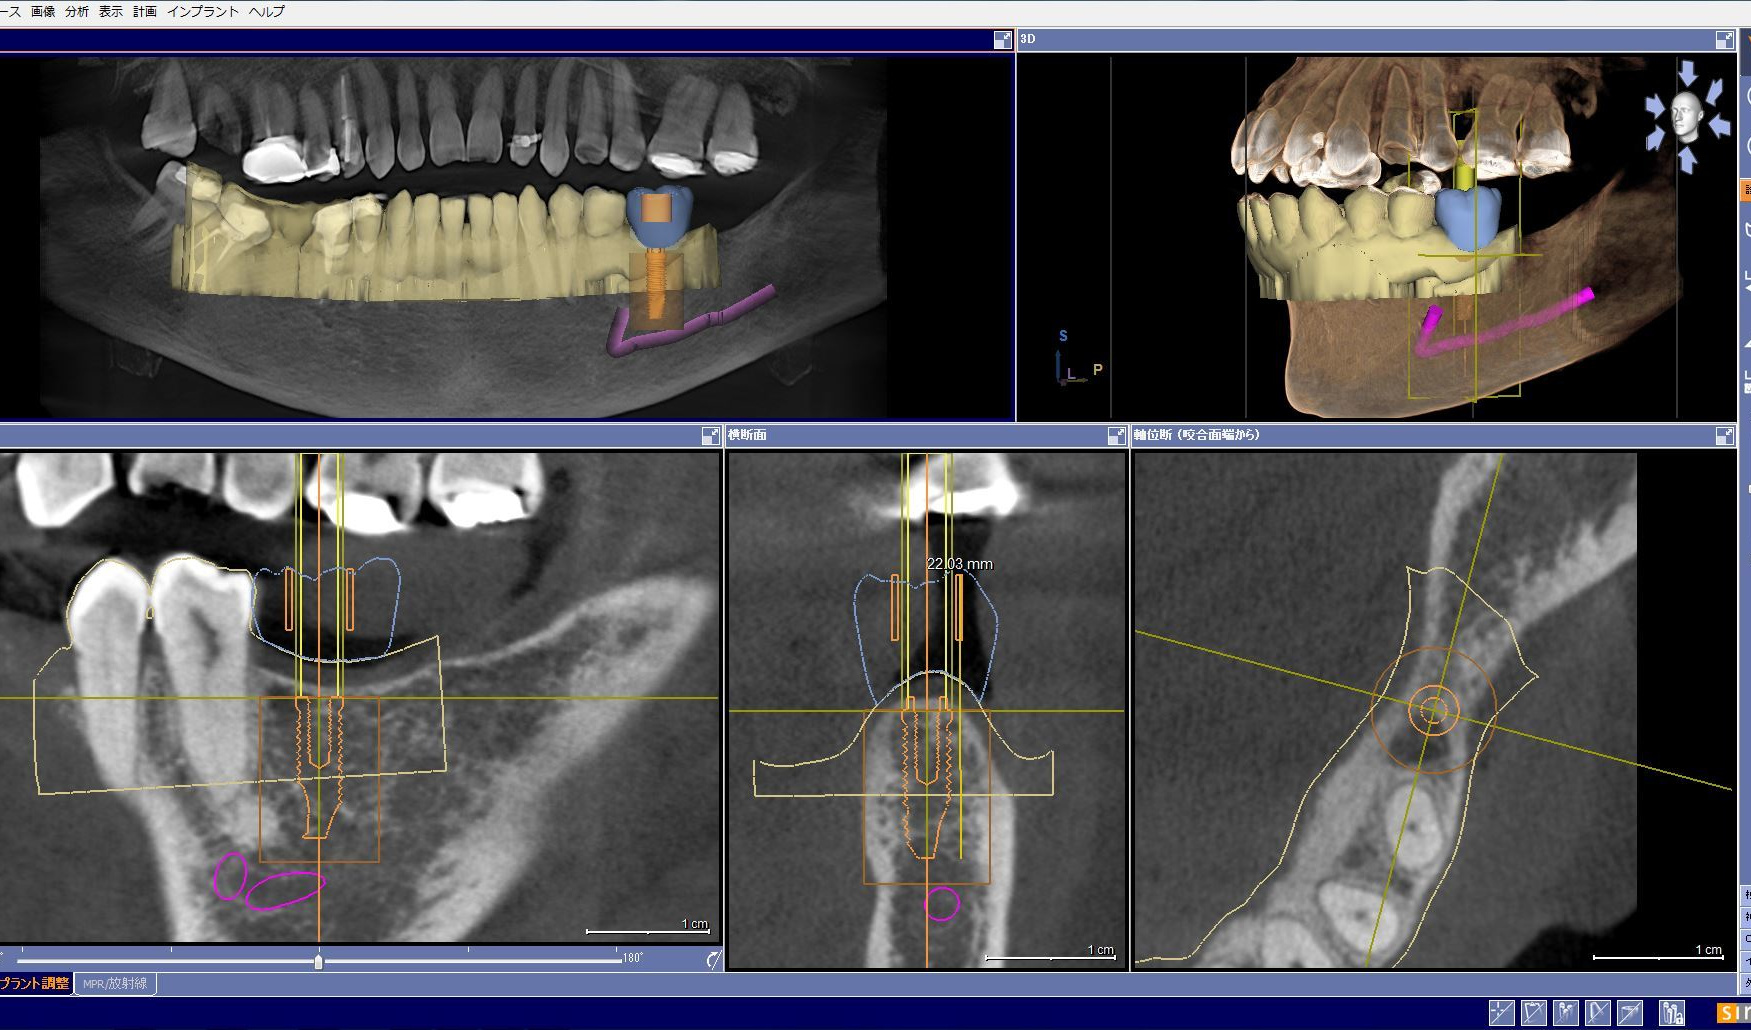

また、歯科用CAD/CAM装置セレックを用い最終的な被せ物をプランニングし、埋入位置を決

定し、可能な限り手術用ガイドを作製しております。

さらにセレックを用いて最終上部構造も作成しております。

セレックとコラボしたシミュレーション

|

外科手術用ガイド(セレックで作製)

最終上部構造のプランニング(セレック)